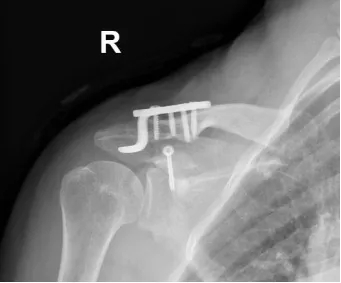

Ììçá?¹Ç¿ÆÊÖÊõ»úеÈË¡¢OÐαÛÍŽḨÖúϼçëιÇà¹Í»¹ÇÕÛÄÚÀο¿Î¢´´ÊÖÊõ

ÊõºóXÏ߯½Æ¬ÏÔʾÄÚÀο¿Î»ÖÃÓÅÒì